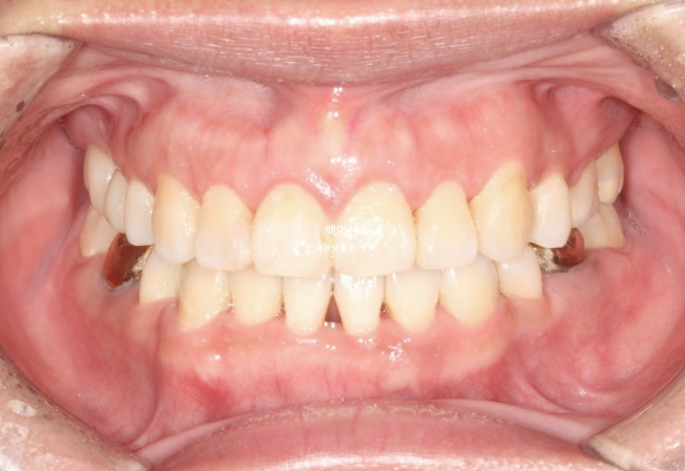

중심선을 잘 맞으며 아래턱 비대칭에 의한 반대교합은 해소되었습니다. 교정으로 턱뼈 자체를 바꿀 수는 없지만 최소한 치아중심선을 맞춰줄 수 있습니다.

아쉬운 점으로는 아래 앞니 블랙트라이앵글입니다.

치간삭제를 더 하면 블랙트라이앵글 사이즈를 줄일 수 있지만, 환자분이 무리한 치간삭제를 원치 않아 많은 양은 진행하지 않았습니다.

25.06

교합은 1급 교합관계를 보이며 물샐틈없이 좋습니다.